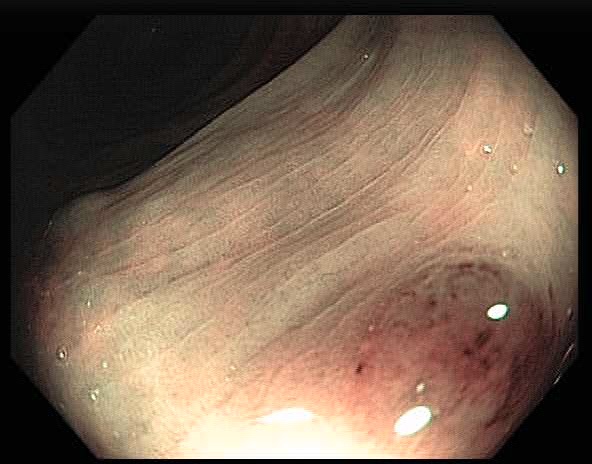

Colonoscopy is the main diagnostic procedure to detect and recognize polyps located on colorectal walls. The accurate detection and correct classification depend on the skills and experience of the endoscopists, however, even for experienced endoscopists, working on conventional colonoscopy for long hours leads to mental and physical fatigue and degraded analysis and diagnosis. Other factors that may affect the classification results include varying illumination conditions, variant texture and appearance, and occlusion. Moreover, different types of polyps are hard to differentiate since they may exhibit a very similar appearance with a subtle difference, as shown in Fig 1. It requires a thorough examination of fine details to distinguish one category form the other. Therefore, an accurate and effective automatic computer-aided system for colonoscopy is required to help endoscopists to detect and classify the type of polyps. This automated recognition mechanism can also be used as a second opinion to determine whether a further biopsy is required for diagnosis, which in turn will greatly reduce the cost of diagnosis. In addition, such an intelligent system can also be used as an educational resource for gastroenterology trainees to reduce the learning curve and cost.

![]() |